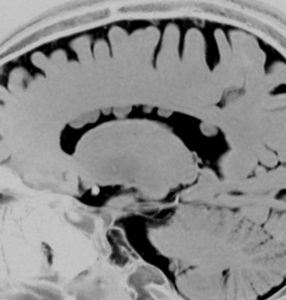

経皮質法 transcortical approachで摘出した後のMRI画像です。手術中には腫瘍からの出血は多く,深い位置にあり脳質壁を損傷しないように全摘出するのは難しいものでした。その後10年以上たっていますが再発していません。

この例は結節性硬化症を伴わないものでした。